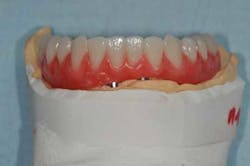

Fig. 14: Hybrid screw-retained mandibular prosthesis

Fig. 15a, b: Final result (removable complete denture on the maxillary)